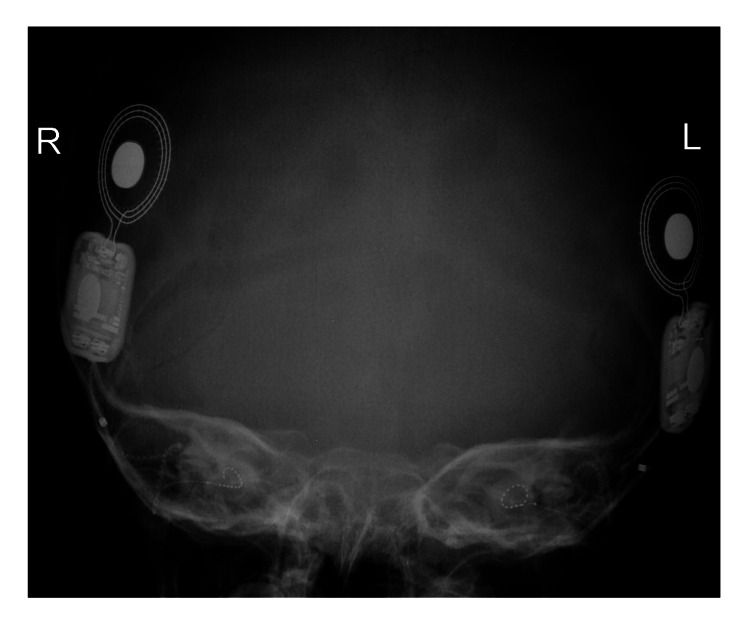

一名 14 個月大的女童,有全身發(fā)育遲緩、畸形特征(眼距過遠、眼球突出、上瞼下垂、小頜畸形)和弱視病史,被轉(zhuǎn)診至佳學(xué)基因遺傳病罕見病基因檢測案例協(xié)作單位。就診原因是言語和語言發(fā)育遲緩。 她的父母是一級近親,被診斷患有雙側(cè)重度至極度SNHL,并在 9 個月大時安裝了雙側(cè)助聽器。 然而,在隨訪中沒有發(fā)現(xiàn)使用助聽器有明顯的好處。 磁共振成像 (MRI) 顯示胼胝體有效發(fā)育不全(圖 1)。 此外,全外顯子組測序顯示 LRP2 基因突變,證實了 DBS 的診斷。 在 18 個月大時,她的智商測試成績?yōu)?75 分。

An external file that holds a picture, illustration, etc.

Object name is cureus-0014-00000021063-i01.jpg

病例 1 的 MRI:(A) 矢狀切面 (B) 冠狀切面顯示胼胝體有效發(fā)育不全